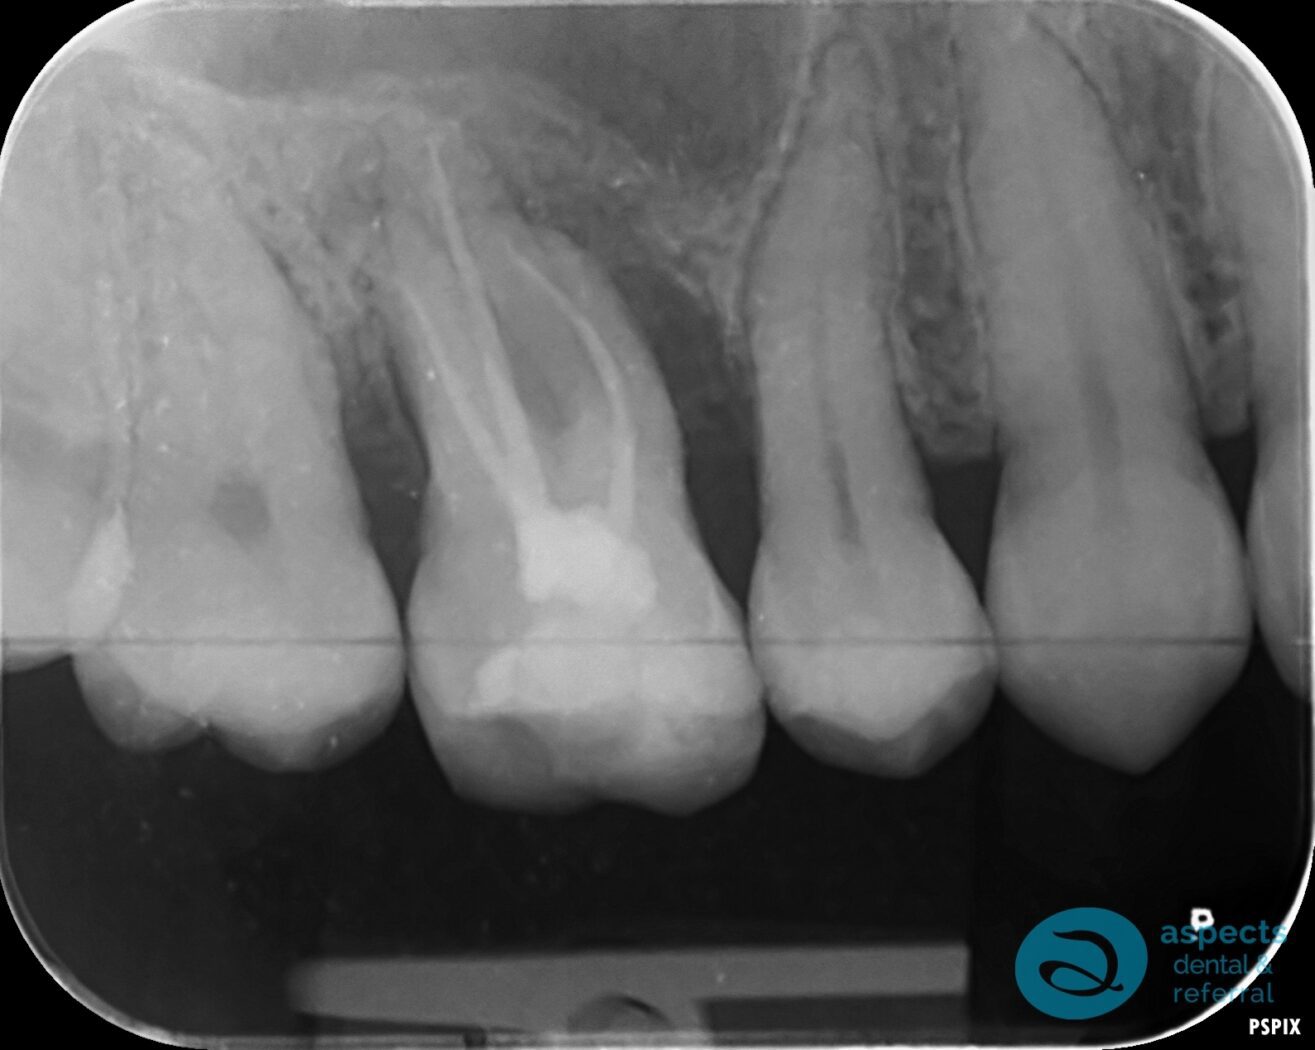

Our Dental Patient presented with a failing Root Canal Treated Tooth, with clinical and radiographic findings indicating an underlying crack. The tooth roots were in close proximity to the maxillary sinus, and significant bone loss was noted in the area.

Before Tooth Extraction & Dental Implant Xray